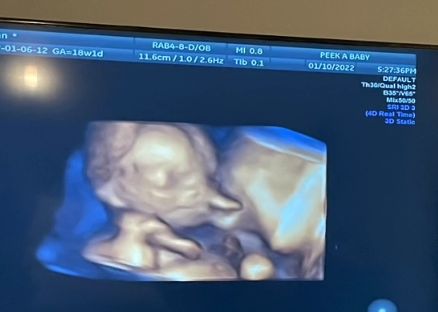

Tradycyjne dwuwymiarowe badanie ultrasonograficzne pozwala obserwować przekrój wnętrza macicy i zarysu ciała płodu oraz jego narządów wewnętrznych. Dzięki temu można ocenić wielkość, kształt poszczególnych części ciała płodu, budowę i położenie łożyska oraz ilość wód płodowych.

Z kolei USG 3D rekonstruuje obraz płodu i wnętrza macicy w prezentacji trójwymiarowej, pozwalając tym samym uzyskać obraz dziecka, który będzie zrozumiały nie tylko dla medyków, ale również przyszłych rodziców.

Dzięki trójwymiarowemu obrazowi można także szybciej i łatwiej zdiagnozować niektóre choroby genetyczne i wady wrodzone jeszcze na wczesnym etapie ciąży. USG 3D ma duże znaczenie w diagnostyce m.in. zespołu Downa. Coraz popularniejsze jest także badanie USG 4D, które pozwala na śledzenie płodu w czasie rzeczywistym.

Ginekolodzy zalecają wykonanie badania USG przynajmniej trzy razy w ciągu całej ciąży: między 11. a 14. tygodniem, około 20. tygodnia ciąży i po 30. tygodniu ciąży.